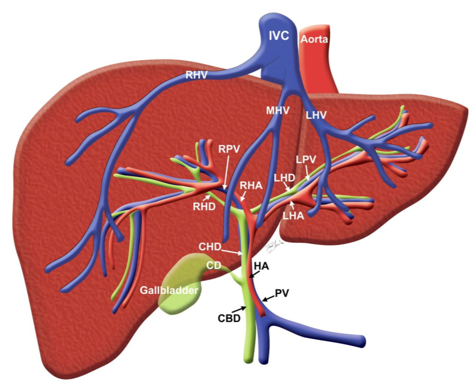

成年人的肝脏约重1200-1600g,是人体内唯一的接受双重供血的器官。正常人肝窦每分钟接受血液约1500ml-2000ml,其中门静脉血流量占总流量的70-80%,肝动脉血流量占20-30%。

肝脏是具有多种生理功能的最大腺体器官。既是物质代谢中心,又是重要的分泌、排泄、生物转化和屏障器官,还是多种凝血因子合成的场所。

肝脏的微循环是指门静脉与肝动脉终末支经肝窦至细小肝静脉(中央静脉)间的循环。

肝脏微循环有两大特征:

有门静脉和肝动脉两个输入系

相当于毛细血管的肝窦有其独特的结构特点

肝脏淤血导致了门脉压力升高,肝功能代谢异常。所以缓解或解除肝脏淤血,降低门脉压力是最迫切的任务。

由于肝脏双重供血及微循环结构的特点,是各种转流手术得以实施的生理基础。